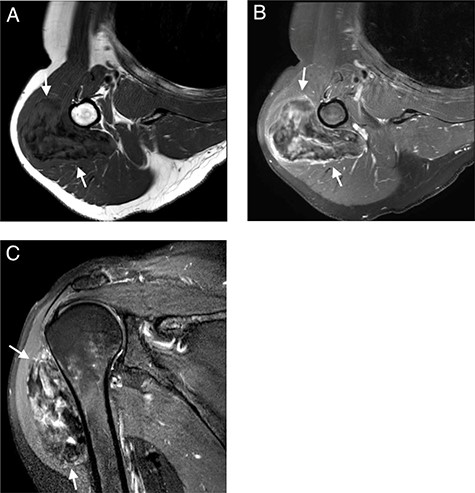

MRI with (A); axial T1-WI; (B) axial T1-FS-WI after administration of intravenous gadolinium contrast and (C) sagittal T2-FS-WI. Heterogeneous tumoral mass indicated with long arrows.

Subsequent MRI showed a well-circumscribed ovoid mass beneath the deltoid muscle abutting the humeral bone without evidence of invasion of the bone or the adjacent neurovascular structures. The mass was heterogeneous isointense to muscle on T1 and heterogeneous hyper- and isointense to muscle on T2-fat-saturated images, embedded were multiple T1 and T2-fat-saturated hypointense foci, suggesting the possibility of internal calcifications or fibrous strands (Fig. 2A and C). The mass showed limited peripheral enhancement and septae, with a slow initial phase and plateau on dynamic contrast-enhanced images (Fig. 2B). No diffusion restriction was noted.